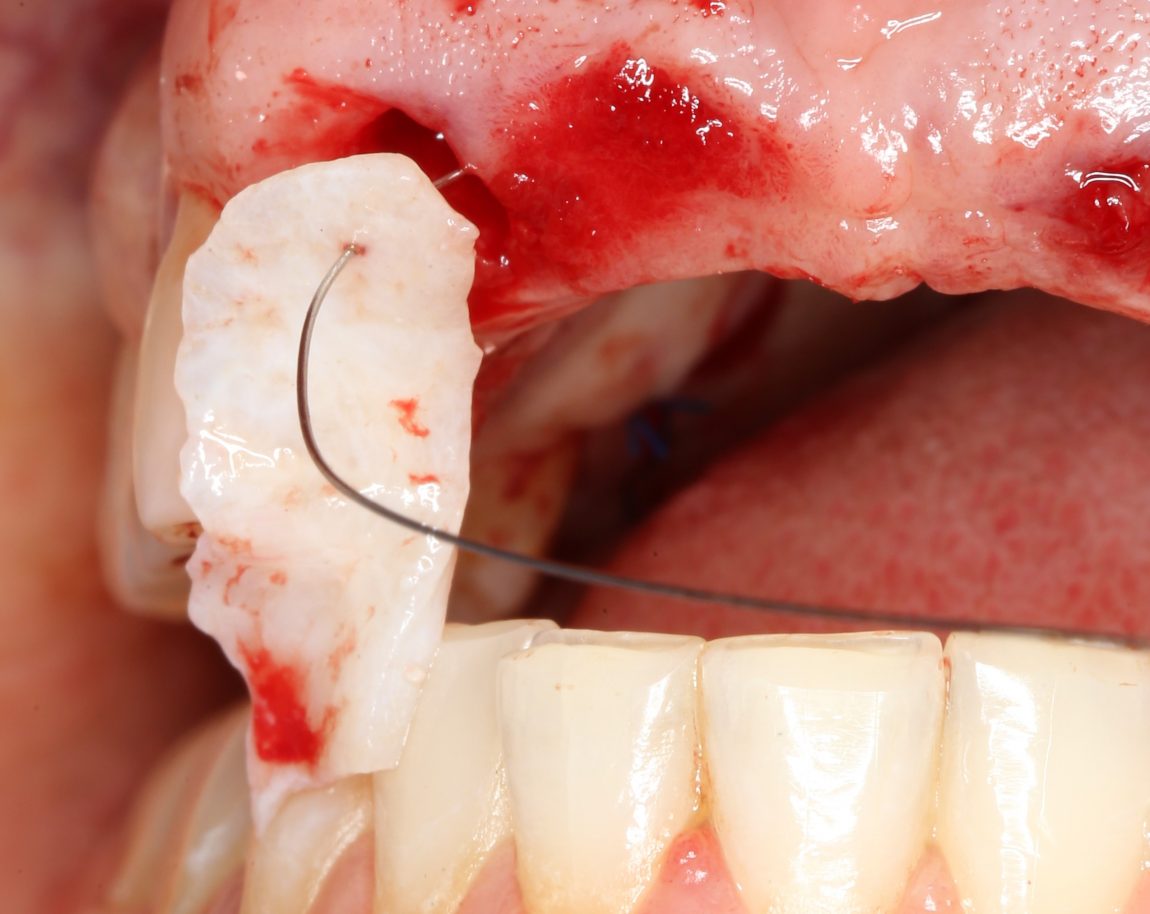

В качестве донорского участка мы выбираем отдел твёрдого нёба ближе к бугру верхней челюсти. Забор аутотрансплантата осуществляется методом расщепления:

При подходящих условиях и правильной реализации, это довольно комфортная для пациента методика получения аутотрансплантатов. При этом, они просты в обработке и почти деэпителизированы — нужно снять лишь тонкий слой эпителия «с торца» трансплантата:

Теперь нам нужно провести и зафиксировать его в тоннеле между лунками удалённых зубов. Для проводки мы решили использовать ортодонтическую проволоку. Как показала практика, это очень удобно и легко.

Суть такова. Сначала мы проводим проволоку через тоннель:

Затем прокалываем ей аутотрансплантат и проводим конец со стороны нанизанного трансплантата обратно:

Таким образом, можно легко и малотравматично «протащить» аутотрансплантат любого размера в сформированный тоннель любой длины: